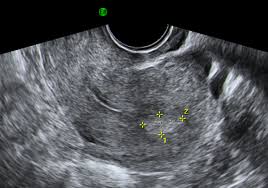

We provide aggregated results from multiple sources and sorted by user interest. You can always come back for endometrial polyp icd 10 code because we update all the latest coupons and special deals weekly. You may browse the classification by using the hierarchy on the left or by using the search functionality. 2 what is polyps in uterus. Endometrial polyps are benign nodular protrusions of the endometrial surface, and one of the entities included in a differential of endometrial thickening. They come from the tissue that lines the uterus, called the endometrium. Please note that this database does not guarantee reimbursement. Endometrial polyps are common findings, both in women with and without gynaecological symptoms.

Endometrial polyps are overgrowths of endometrial glands that typically protrude into the uterine cavity. The uterus is primarily made up of muscle fibers but has an inner lining made up of endometrial tissue. Endometrial polyps are rare among women younger than 20 years of age. They come from the tissue that lines the uterus, called the endometrium. Endometrial polyps are benign nodular protrusions of the endometrial surface, and one of the entities included in a differential of endometrial thickening.

Endometrial polyps are overgrowths of endometrial glands that typically protrude into the uterine cavity.